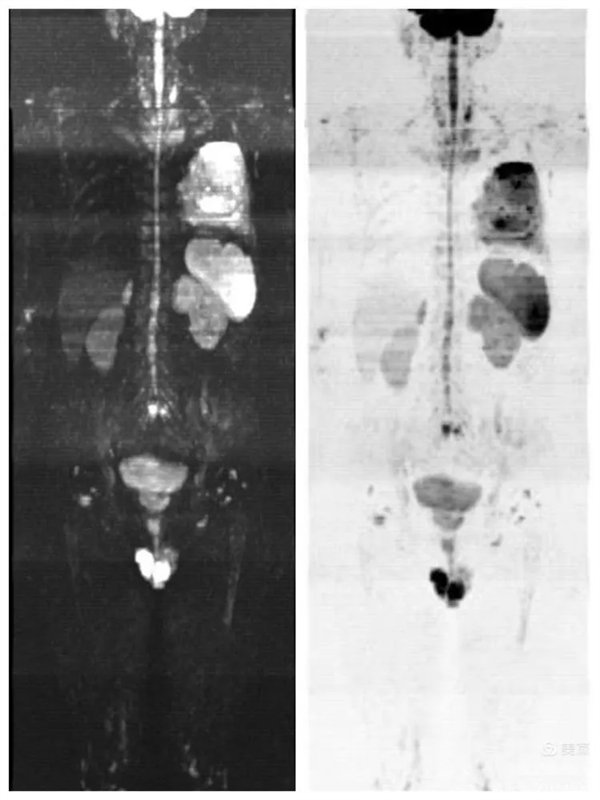

圖2:全身彌散成像反轉(zhuǎn)圖

圖3:全身彌散成像偽彩圖

圖4:彌散成像圖與類PET圖組合